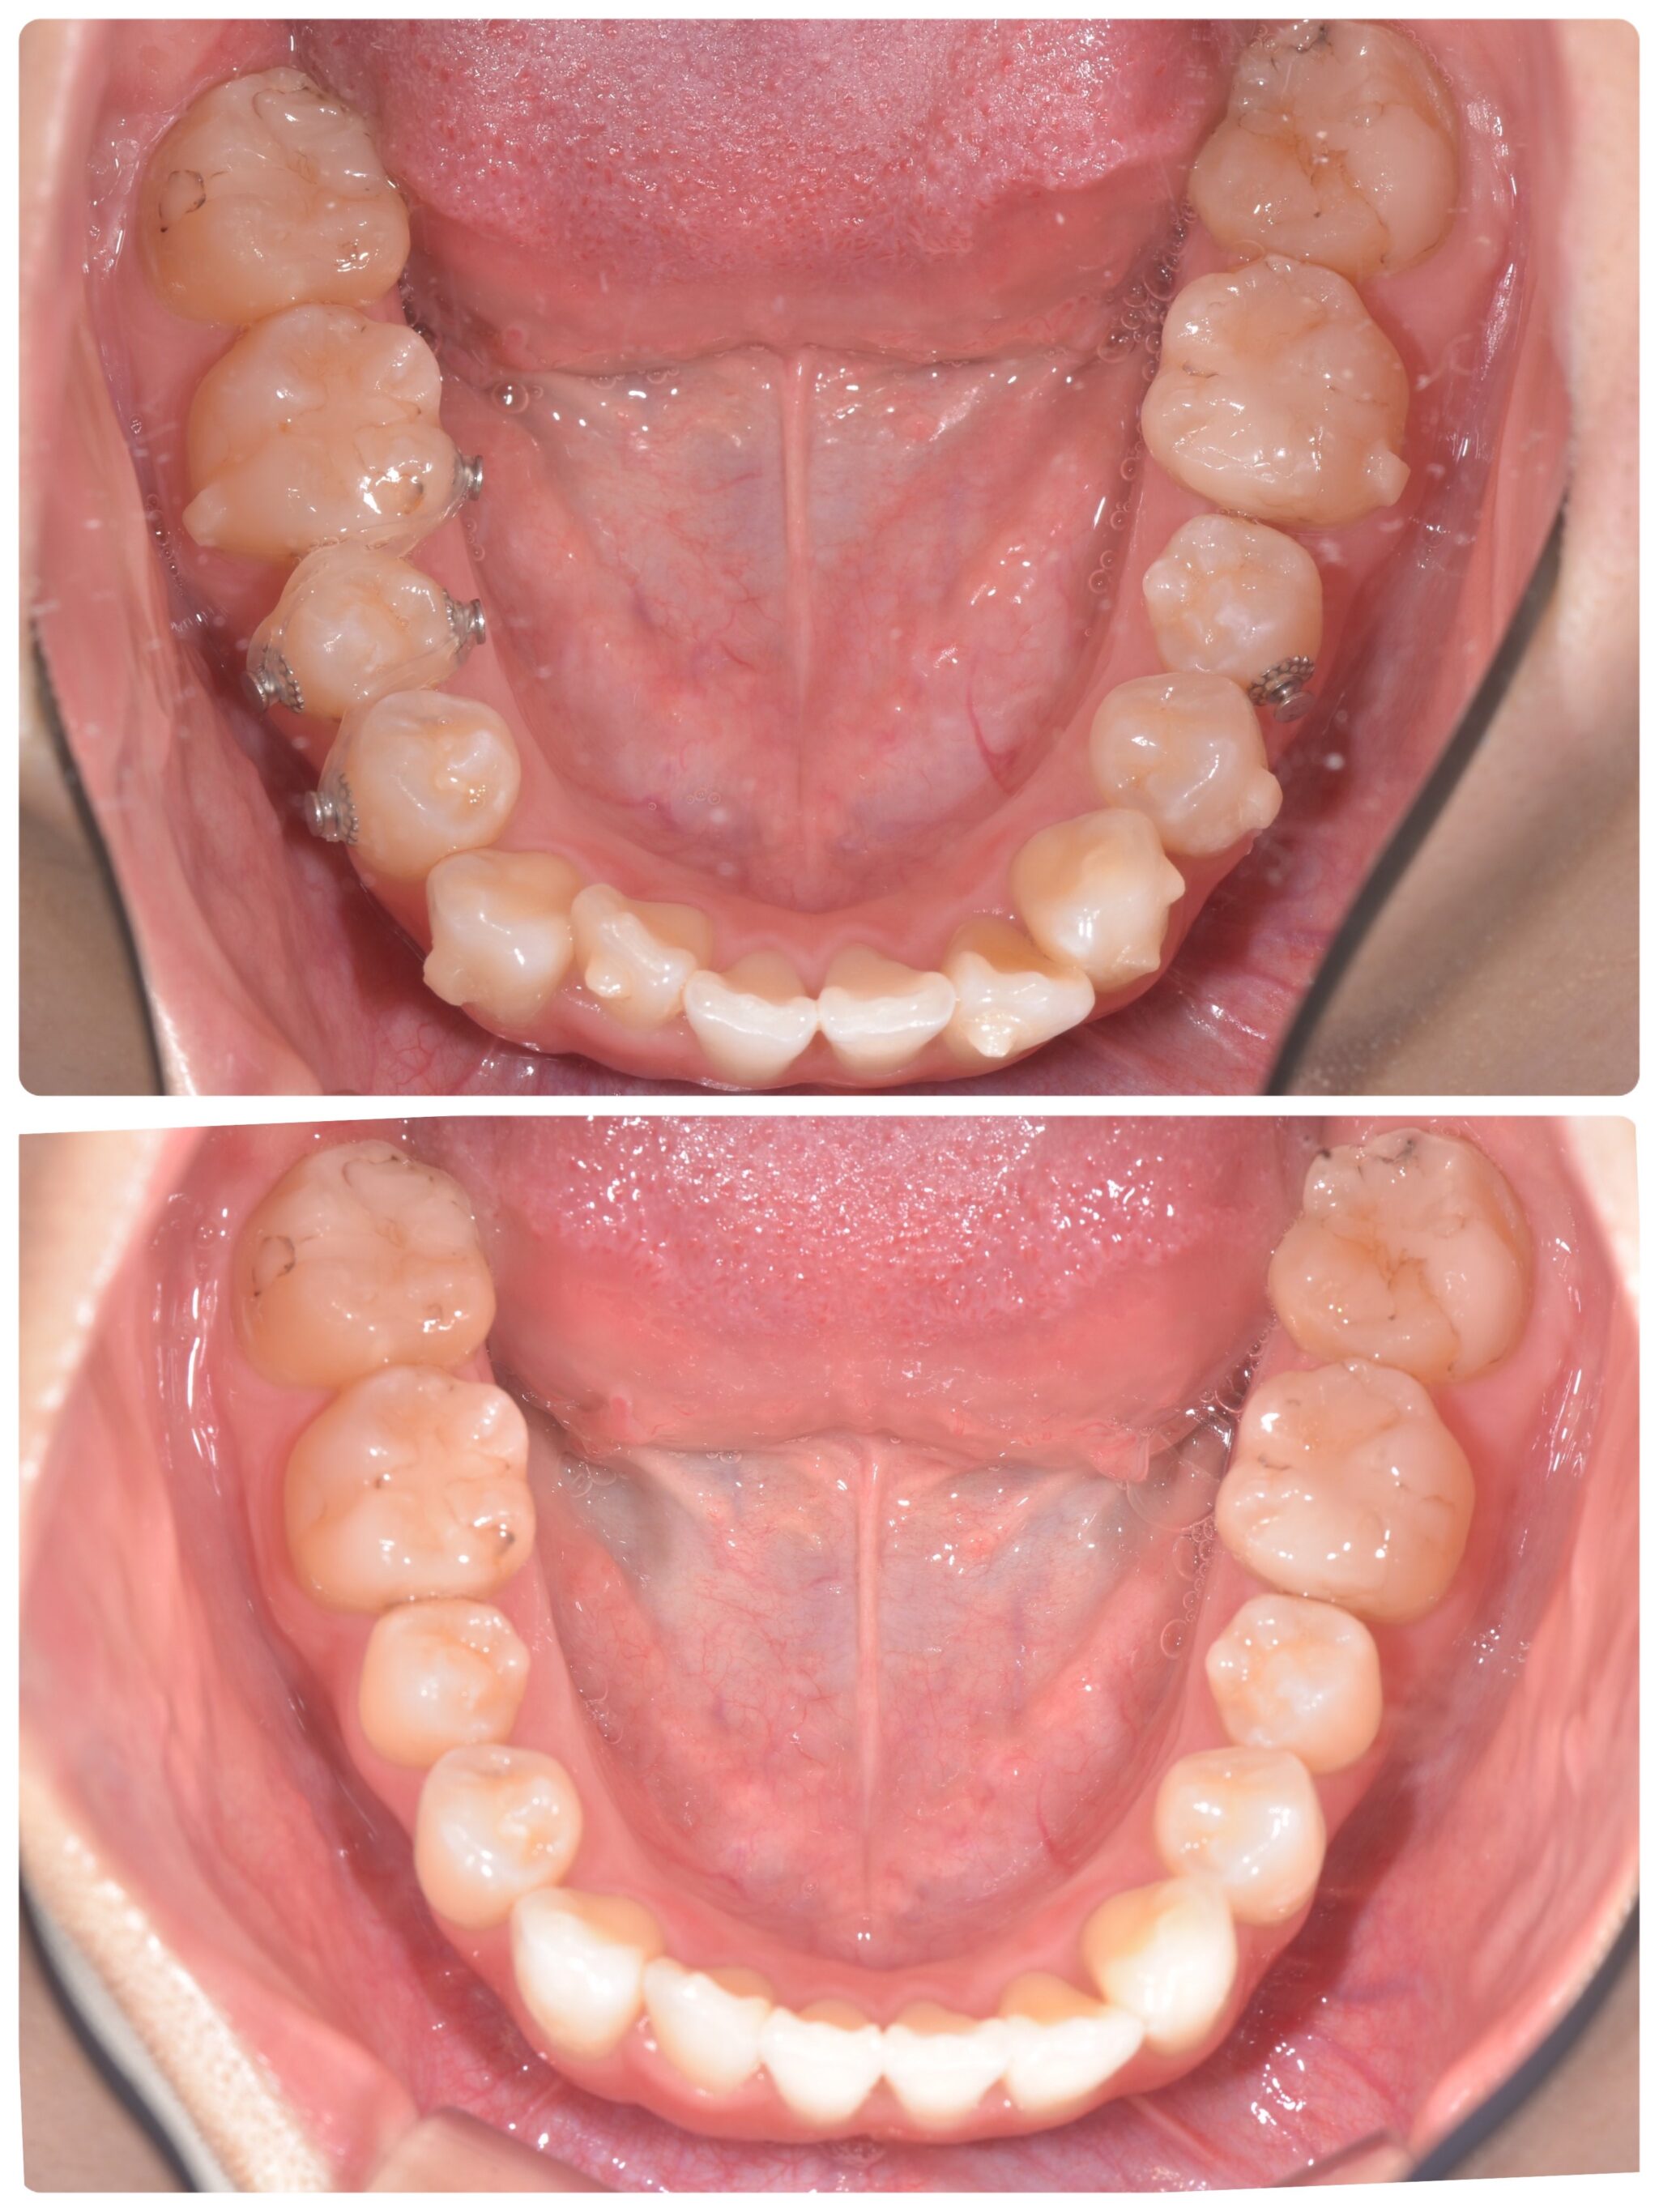

その後の下の歯の経過です。

ゴムをつけてから、ある程度動かしたあと

3ヶ月経過しました。

インビザラインを初めてからは6ヶ月になります。

写真左側の奥から3番目の歯の捻れは、かなり改善されました。

右側も前に比べて、捻転が改善されているのが分かります。

下の前歯のガタつきも揃ってきました。

この後、更に理想の歯並びにするため、追加のマウスピースを作成

していくことになりました!